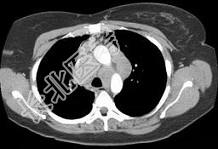

- 单项选择题女,33岁, 咳嗽,乏力, 低热,皮肤有结节, 结合CT图像,最可能的诊断是 ( )

D、结节病